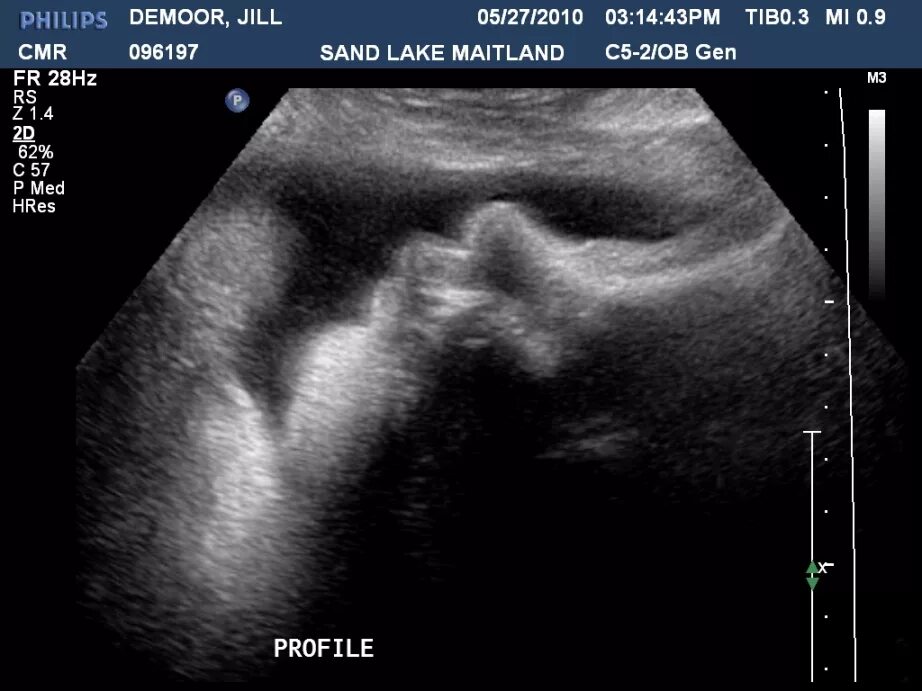

38 3 недель беременности